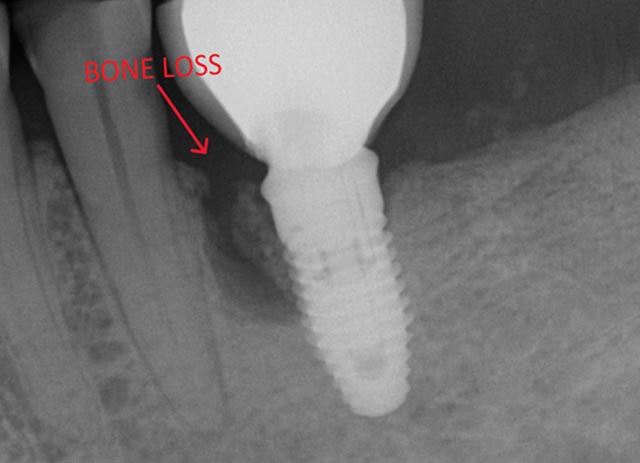

Implant Bone Grafting - Before And After